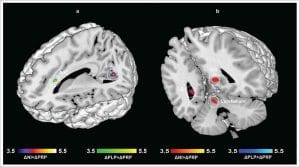

V úlohách rozpoznávania nepríjemných podnetov sa medzi účastníkmi z placebovej alebo kontrolnej skupiny a šťastnejšími účastníkmi zo skupiny s probiotikami prejavil jasný rozdiel – doslova: Funkčná analýza magnetickej rezonancie ukázala, že určité oblasti mozgu boli silnejšie prekrvené, a teda viac aktivované. Konkrétne sa aktivovali oblasti mozgu zodpovedné za výkonnosť pamäte, zlepšenie motorických schopností a vyššiu pozornosť. To sa prejavilo aj v miere rozpoznania: zatiaľ čo kontrolná skupina alebo skupina s placebom rozpoznala menej ako 70 % opätovne zobrazených obrázkov, v skupine s probiotikami bolo rozpoznaných dokonca viac ako 85 % obrázkov.

Okrem toho sa skúmali emocionálne rozhodovacie procesy. Aj v tomto prípade sa prejavil významný pozitívny účinok: účastníci zo skupiny užívajúcej probiotiká boli vysoko koncentrovaní, a preto boli vo svojom rozhodovaní sebavedomejší a jednoznačnejší.

Táto štúdia poskytla jasné dôkazy o tom, že podávanie tohto konkrétneho viacdruhového probiotika viedlo k výraznému zlepšeniu koncentrácie a pamäti, ako aj k pozitívnym emocionálnym dojmom a že užívatelia probiotík boli vo svojich rozhodnutiach výrazne sebaistejší a jasnejší.

© Bagga et al. (2018), DOI 10.1080/19490976.2018.1460015